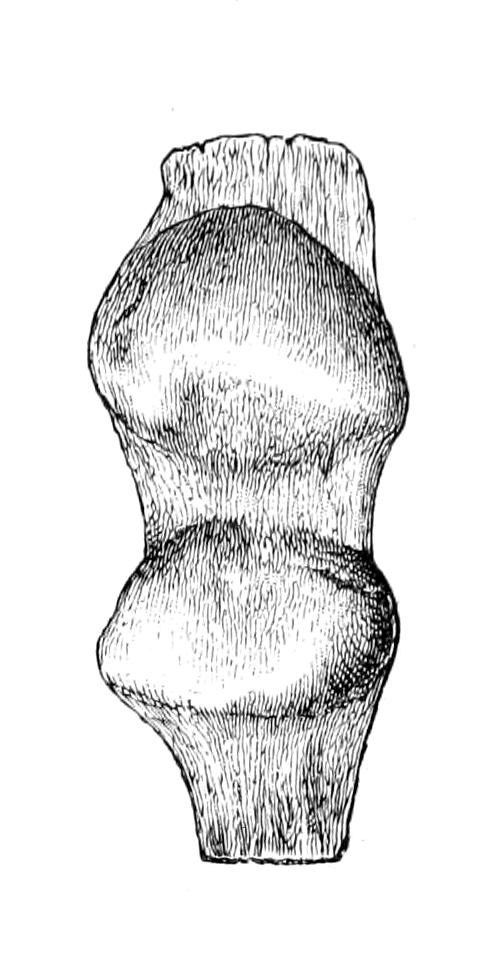

Fig. 1

Congenital hypertrophy: gigantism of both lower extremities. (Case of Dr. Graefe [Sandusky].)

A. Physiological Hypertrophy.

—1. This includes many of the compensatory enlargements of an organ or a part when extra work is put upon it, owing to deficiency of some other organ or part. This is spoken of as compensatory enlargement. Illustrative examples may be seen in the heart, which becomes larger and stronger when the bloodvessel walls are diseased and their lumen narrowed, or when other obstructions to circulation are brought about; again, in enlargement of one kidney after extirpation of the other, or of the wall of the stomach when the pylorus is constricted or obstructed; again, of the fibula after weakening or more or less destruction of the tibia, or of the shaft of any bone when it has been weakened at some point by not too acute disease; or, again, of the walls of bursæ after constant friction.